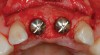

Figure 11  Periapical radiograph at the time of provisionalization. Note the wide peak of bone between implants Nos. 8 and 9.

Figure 11

Figure 12  Buccal view of the implants immediately after provisionalization. Even at the temporary stage, the soft tissue closely mimicked the original periodontal drape.

Figure 12